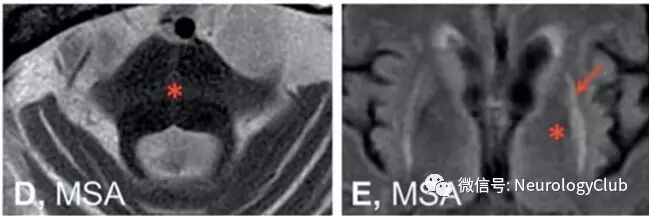

图2:在磁共振扫描中,脑干的正中矢状位提示帕金森氏病(PD)患者无明显特异性萎缩(图A),进行性核上性麻痹(PSP)患者可见中脑萎缩(*)(图B),多系统萎缩(MSA)患者可见脑桥萎缩(*)和小脑上蚓部萎缩(#)

图3:还有一些磁共振征象可以提示MSA,但并非高度敏感性的。T2WI序列脑桥可出现十字形高信号(脑桥十字征,*,图D),壳核可见低信号(*)伴边缘边缘高信号(壳核裂隙征,,图E